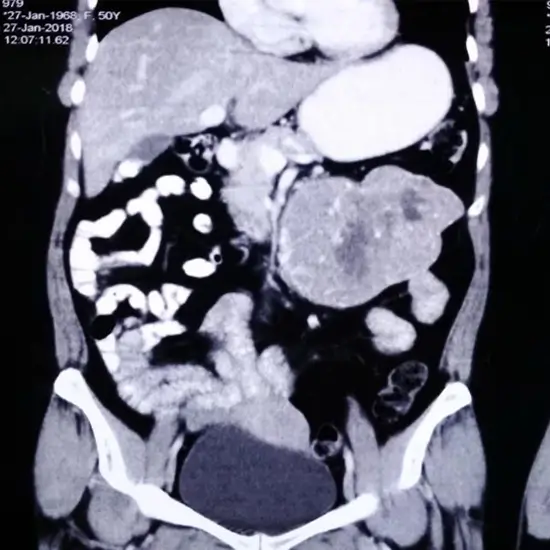

CECT Upper Abdomen

CECT Upper Abdomen is a contrast-enhanced computer tomography study of the upper abdomen to visualise the internal organs of the upper abdomen and their disease condition.

CECT upper abdomen test scan is a contrast-enhanced scan using contrast for imaging and diagnostic purposes. The scan is used to diagnose abdominal pain, injury, infection of the abdomen etc. Patients need to give information regarding diet, medications and allergies before taking the contrast for the CECT upper abdominal test procedure.